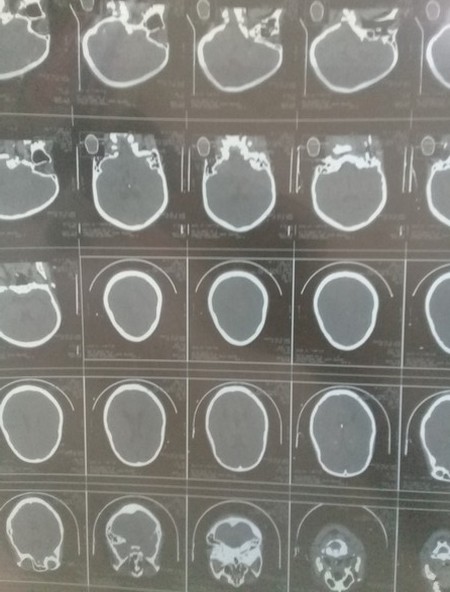

Actuellement elle vient en aide à Khadjetou Diallo une jeune fille ressortissante de la Guinée Conakry venue rejoindre son mari à Nouakchott victime d'un mariage précoce qui a engendrer d'une mort fœtale intra utérine qui l'entraina dans un coma de 10 jours avec complications, après plusieurs jours de diagnostic des radios et analyses, une thrombose veineuse cérébrale à été découverte.

Elle fut admise à l'hôpital National de Nouakchott dans le service de la réanimation avant d'être transférée à l'hôpital neuropsychiatrique de Sebkha.